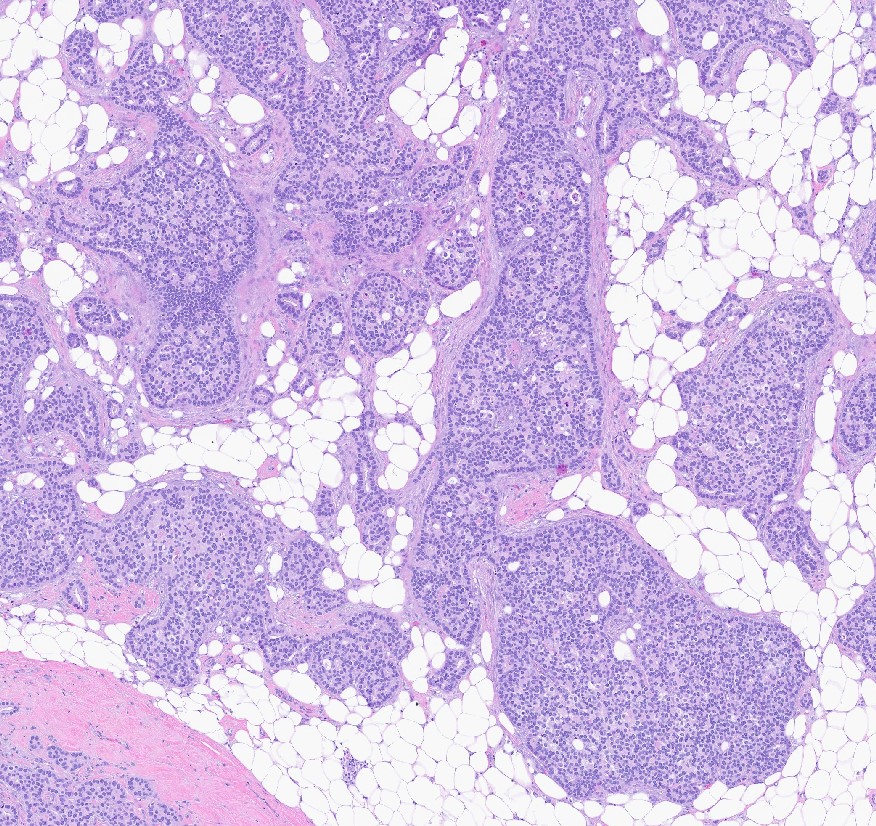

Microscopic (histologic) description

- Histologic grading is based on the Nottingham / modified Bloom & Richardson Score (Histopathology 1991;19:403):

- Tubule formation (1 - 3 points):

- > 75% (1 point)

- 10 - 75% (2 points)

- < 10% (3 points)

- Nuclear pleomorphism (1 - 3 points):

- Small, regular, uniform, similar to normal ductal epithelial cells, 2 - 3x RBC (1 point)

- Moderate increase in size / variability (2 points)

- Large nuclei, marked variation, often vesicular chromatin with prominent nucleoli (3 points)

- Mitotic count (1 - 3 points), dependent on microscopic field area

- Total score (add points for tubule formation, nuclear pleomorphism and mitotic count):

- 3 - 5 points: grade 1

- 6 - 7 points: grade 2

- 8 - 9 points: grade 3

- Histological features of IBC NST vary considerably from case to case and even within the same case

- Margins vary from highly infiltrative, permeating the surrounding tissue, to continuous pushing margins

- Architecture varies from sheets, nests, clusters, cords or individual cells (but lacks the cytomorphological characteristics of invasive lobular carcinoma)

- Tubular formations are prominent in well differentiated tumors but absent in poorly differentiated tumors

- 2 distinct growth patterns exist:

- Large and solid nests or syncytial infiltrative growth pattern with little associated stroma and an expansive growth that compresses the surrounding stroma (e.g., most basal-like breast cancers)

- Tumors characterized by small cancer nests accompanied by marked fibrosis (desmoplastic / scirrhous); this type diffusely infiltrates the surrounding tissue as an irregular shaped spiculated mass

- Calcification in 60% of cases, variable necrosis

- Elastosis involves stroma, wall of vessels and ducts and causes grossly noted chalky streaks

- Often ductal carcinoma in situ (DCIS) (up to 80%)

Microscopic (histologic) images

Contributed by Julie M. Jorns, M.D., Kristen E. Muller, D.O., Gary Tozbikian, M.D. and Emad Rakha, M.D.